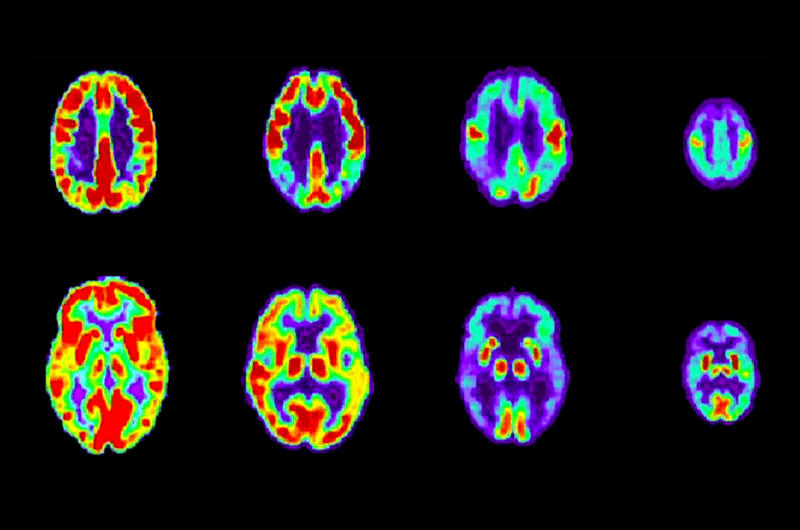

Normal vs. Not Normal Aging: Understanding the Difference